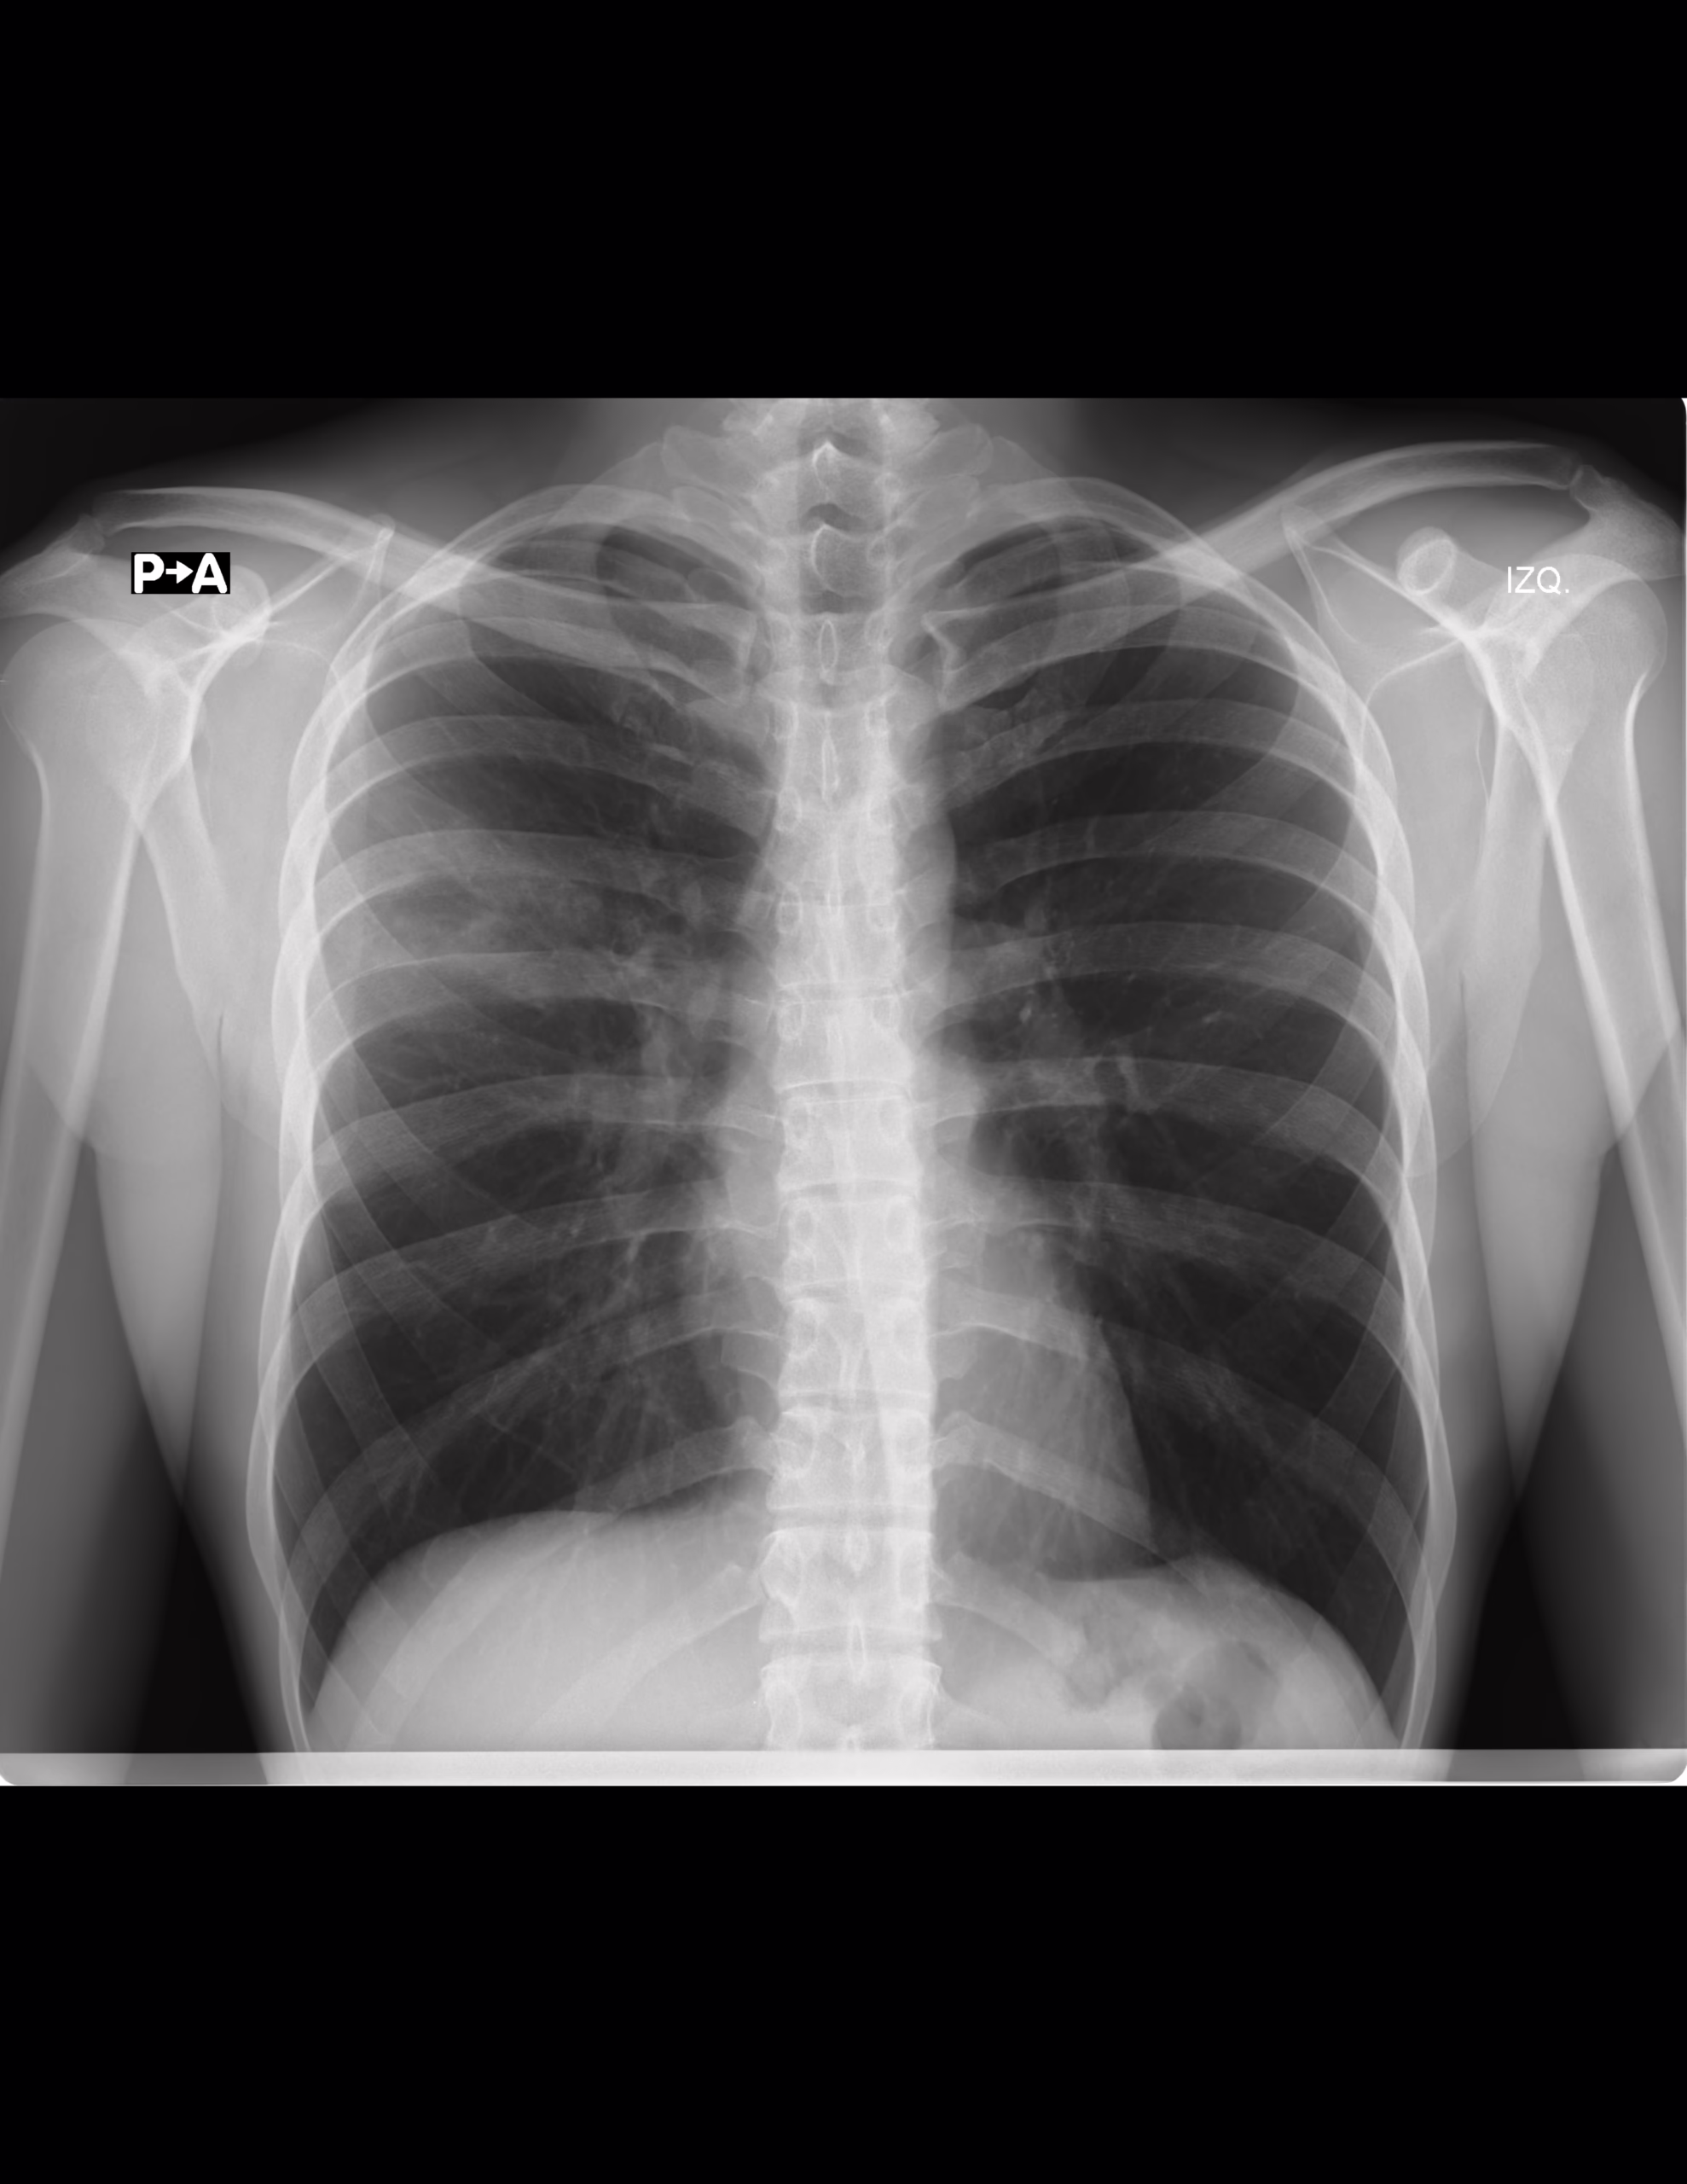

Hallazgos:

La tráquea es central, de calibre normal.

Silueta cardíaca de bordes bien definidos, con índice cardiotorácico de 0.40.

Pulmones con adecuado esfuerzo inspiratorio, se identifica zona de incremento en la radiopacidad de manera difusa en la región parahiliar superior y apical derecha, que tiende a presentar imagen de broncograma aereo asociado.

Los hemidiafragmas con morfología normal, los ángulos diafragmáticos están libres.

Las estructuras óseas con morfología y densidad conservadas.

En los tejidos blandos periféricos no se muestran cambios.

Impresión:

Radiopacidad parahiliar superior derecha, que pudiera corresponder con áreas de ocupación alveolar, se recomienda la valoración con estudios adicionales (TAC) si clínicamente se considera necesario.

Resto sin alteración evidente por este método.